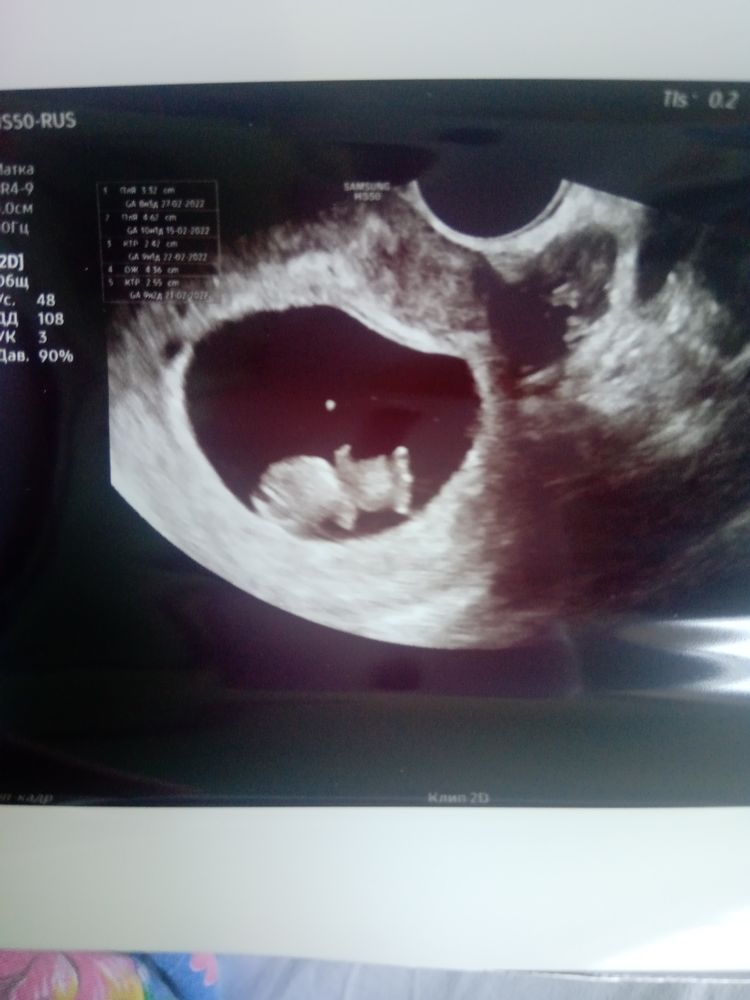

УЗИ, КТГ, доплерВсем привет )делала УЗИ на 10 ой недели беременности, все показатели в норме, сердцебиение есть) Но эмбриончик не двигался, спал?)))

Лизавета, вот моя четвертая в 10 нед ровно. Хвостик, зачатки рук и ног. К одиннадцатой неделе это все есть, за неделю буквально вырастает. Но на десятой (9+ нед) еще нет ничего.